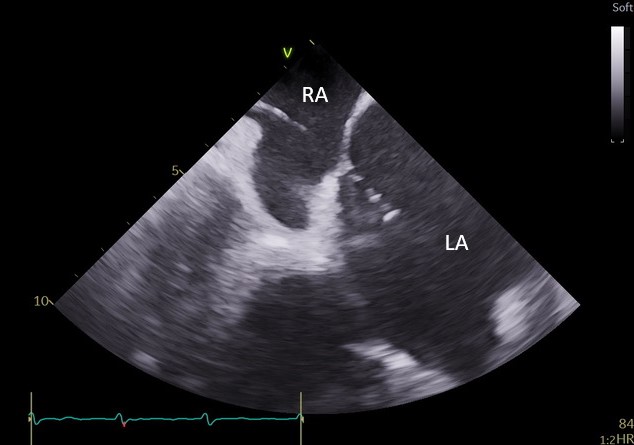

Specjaliści z Pracowni Kardiologii Inwazyjnej I Kliniki Kardiologii UCK przeprowadzili 3 zabiegi zamknięcia uszka lewego przedsionka (ang. LAAO – left atrial appendage occlusion) z wykorzystaniem systemu echokardiografii wewnątrzsercowej (ang. ICE – intracardiac echocardiography).

– U części pacjentów kwalifikowanych do LAAO ryzyko związane z wykorzystaniem obrazowania metodą TEE jest zbyt wysokie ze względu na poważne zmiany chorobowe przełyku. To dotychczas uniemożliwiało wykonanie zabiegu. Obrazowanie metodą ICE pozwala na bezpieczne wykonanie zabiegu zamknięcia uszka lewego przedsionka również w tej grupie chorych, ponieważ specjalną sondę ultrasonograficzną wprowadza się nie do przełyku, lecz przez układ żylny pacjenta, bezpośrednio do jam serca – mówi dr Dariusz Ciećwierz, koordynator Pracowni Kardiologii Inwazyjnej I Kliniki Kardiologii UCK z I Katedry i Kliniki Kardiologii GUMed. – Dodatkową korzyścią tego rozwiązania jest większy komfort pacjenta w trakcie zabiegu, dzięki czemu można uniknąć sedacji czy znieczulenia ogólnego.